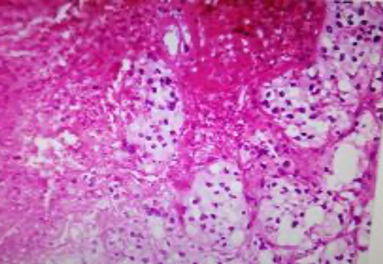

Figs 1 and 2 from a mass in the right hypochondriac region.

Make your diagnosis.

Fig 1 : Giemsa x 100

Fig 2 : Giemsa x 400

Highly suggestive of papillary adeno-carcinoma Endometrium - Shows adequate cellularity with papillae of carcinoma cells showing hyperchromatic and pleomorphic nuclei, highly suggestive of papillary adenocarcinoma of the endometrium.